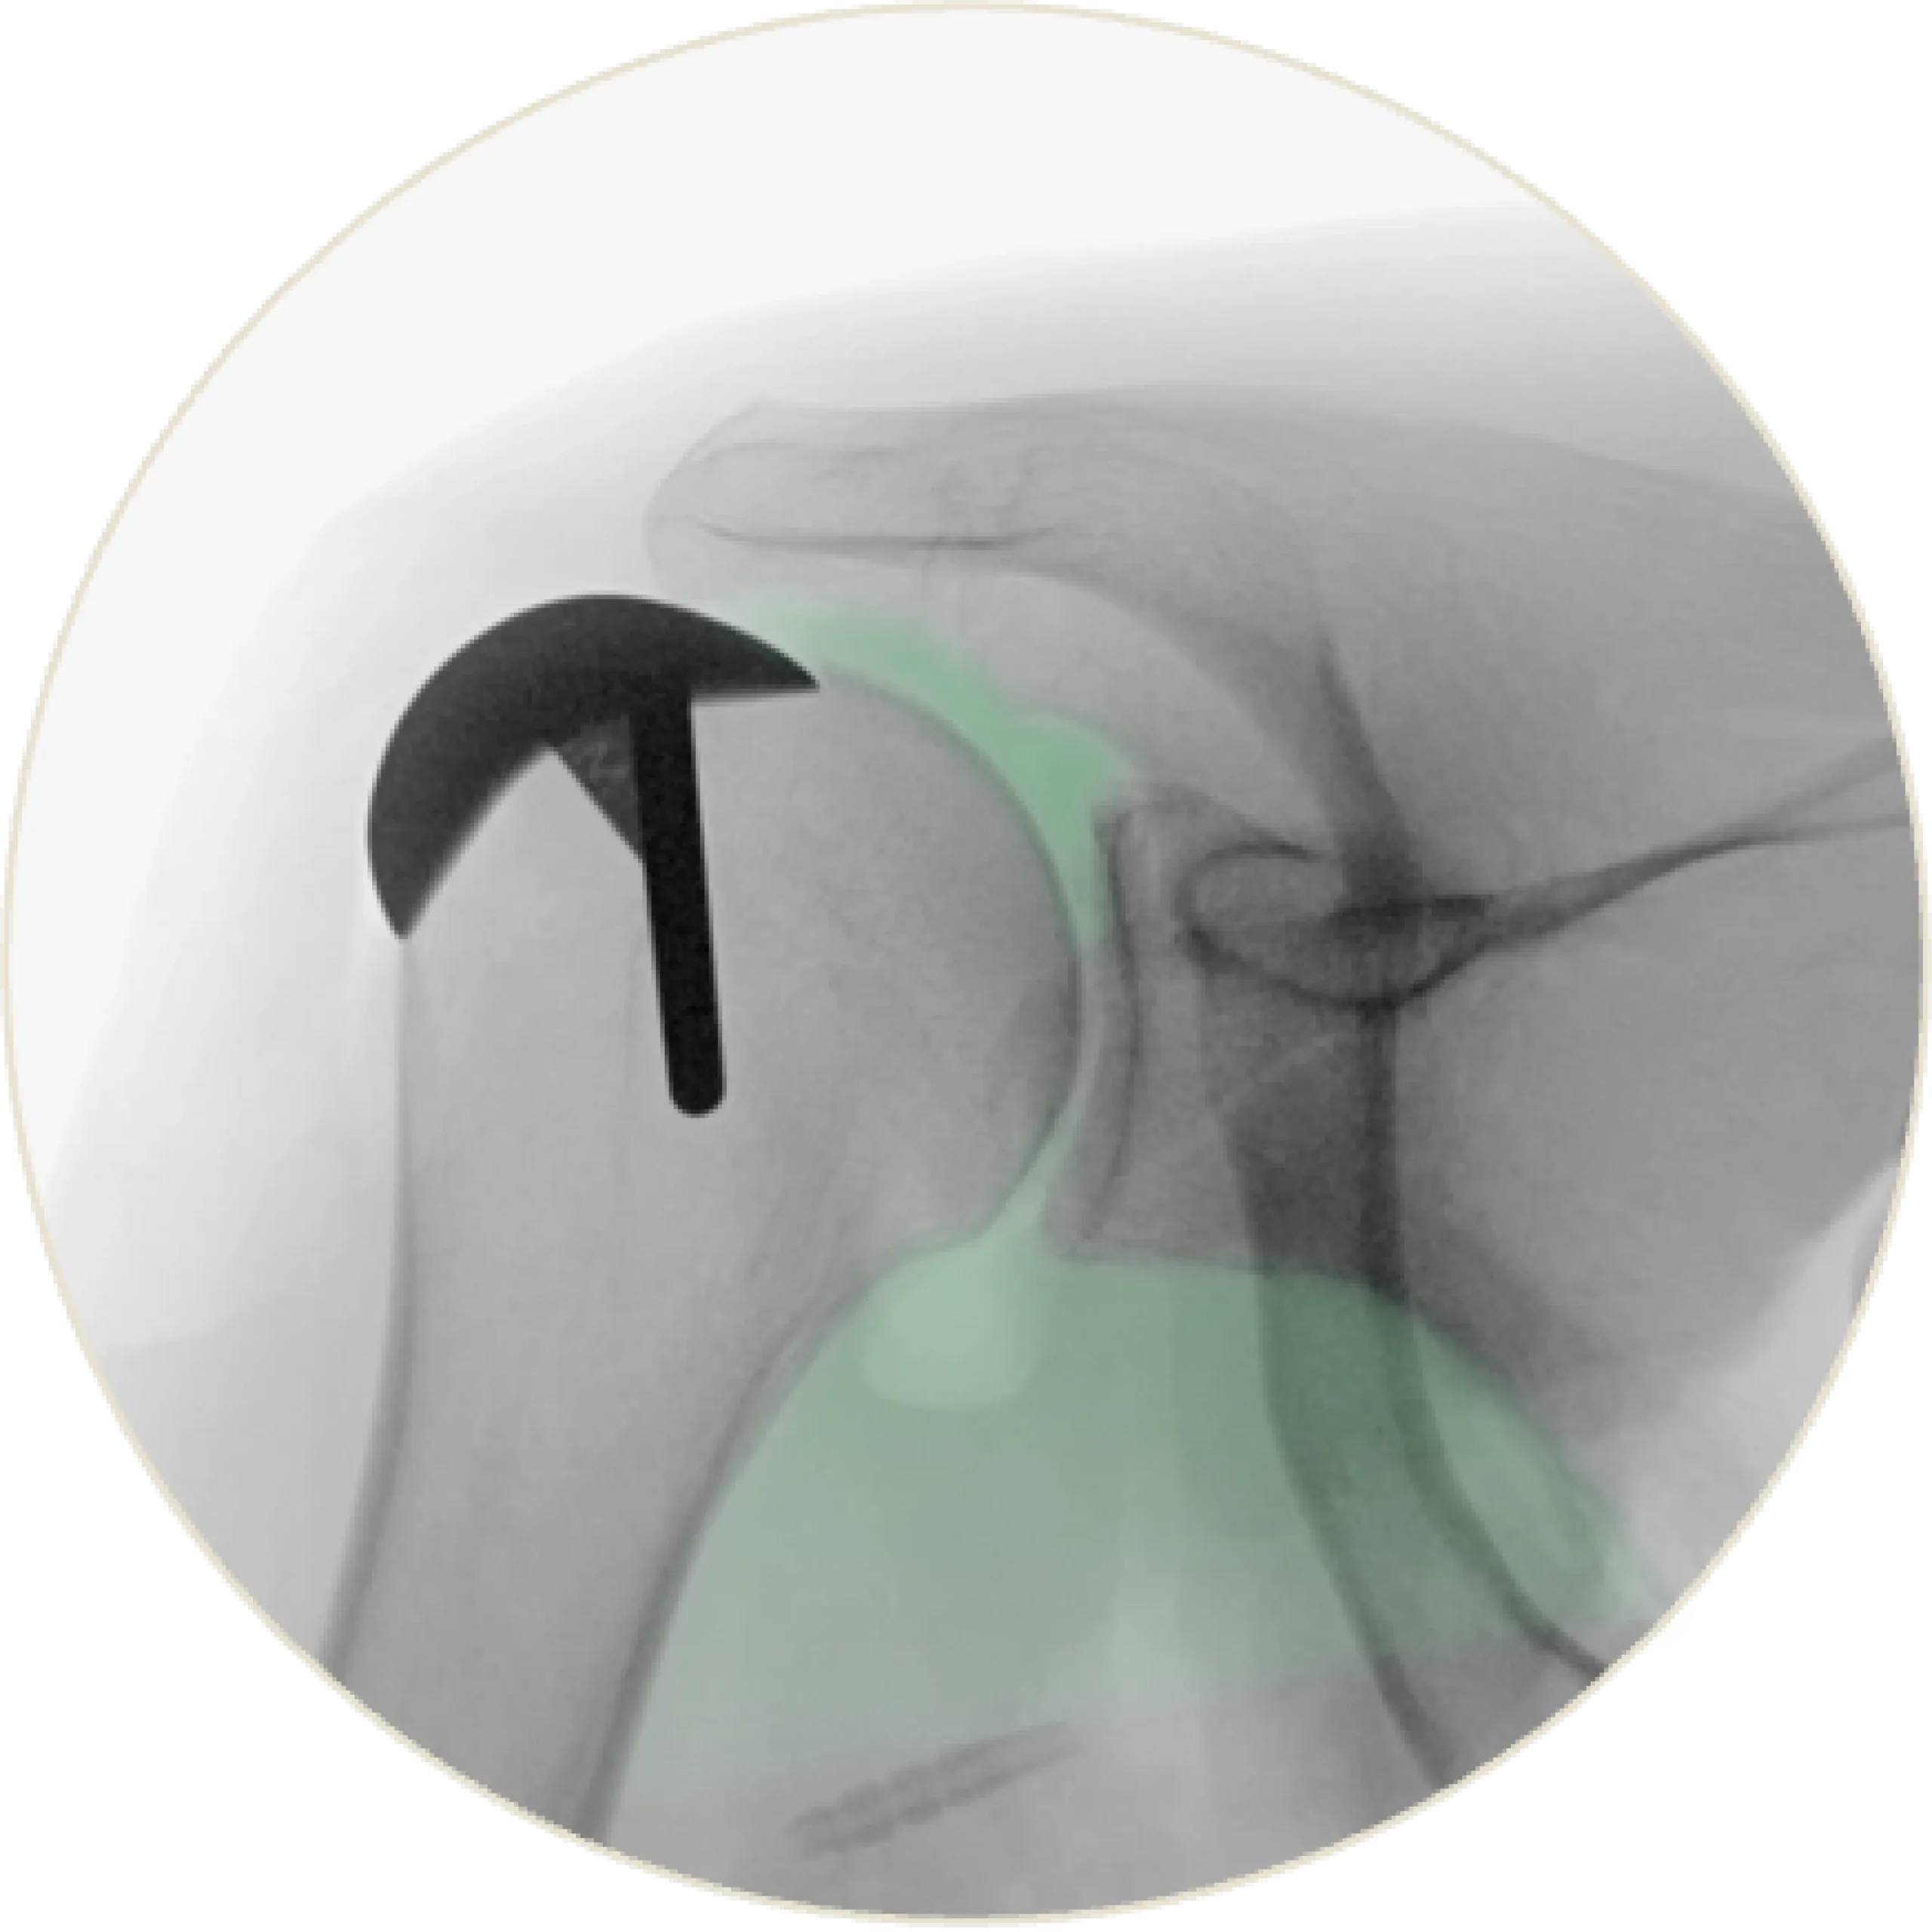

Irreparable Cuff Tear

A irreparable tear causes the humerus to migrate proximally, disrupting natural alignment. This leads to impingement pain, reduced range of motion, and diminished shoulder stability.